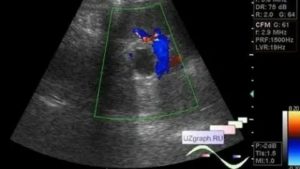

Как выглядит киста яичника на УЗИ

Основной признак кисты яичника на УЗИ – формирование на его теле полого отростка. Он отличается от нормального фолликула тем, что, на протяжении цикла, никак не меняется. К тому же, такое новообразование имеет больший размер.

На снимке УЗИ, киста яичника выглядит черным пятном, размером от 3 до 20 см.

Толщина стенки такого новообразования – вариабельная. Часто она имеет кровеносные сосуды, расположенные циркулярно.